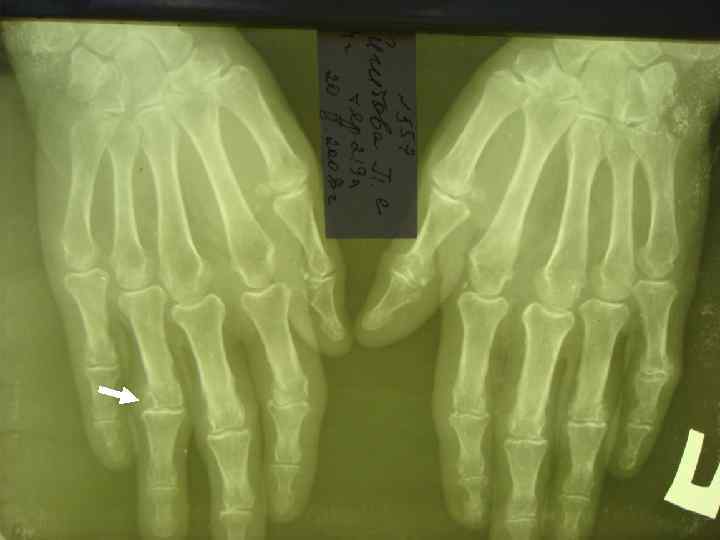

ДИАГНОСТИЧЕСКИЕ КРИТЕРИИ РА (АРА, 1987, 1998) l l l 5. НАЛИЧИЕ ПОДКОЖНЫХ УЗЛОВ В ОБЛАСТИ ЕСТЕСТВЕННЫХ КОСТНЫХ УТОЛЩЕНИЙ И РАЗГИБАТЕЛЬНЫХ ПОВЕРХНОСТЕЙ КОНЕЧНОСТЕЙ ИЛИ ПЕРИАРТИКУЛЯРНО (РЕВМАТОИДНЫЕ УЗЕЛКИ). 6. ОБНАРУЖЕНИЕ РЕВМАТОИДНОГО ФАКТОРА В СЫВОРОТКЕ КРОВИ ИЛИ СИНОВИАЛЬНОЙ ЖИДКОСТИ. 7. ТИПИЧНЫЕ РЕНТГЕНОЛОГИЧЕСКИЕ ИЗМЕНЕНИЯ: ОКОЛОСУСТАВНОЙ ОСТЕОПОРОЗ, ЭРОЗИВНЫЙ АРТРИТ.

R-ЛОГИЧЕСКИЕ СТАДИИ РА (STEINBROCKER, 1949) l СТАДИЯ I — ОКОЛОСУСТАВНОЙ ОСТЕОПОРОЗ БЕЗ l СТАДИЯ II — НЕЗНАЧИТЕЛЬНОЕ СУЖЕНИЕ l СТАДИЯ III — ЗНАЧИТЕЛЬНОЕ РАЗРУШЕНИЕ ХРЯЩА И l СТАДИЯ IV — ПРИЗНАКИ III СТАДИИ + АНКИЛОЗ ДЕСТРУКТИВНЫХ ИЗМЕНЕНИЙ. СУСТАВНОЙ ЩЕЛИ, ЕДИНИЧНЫЕ УЗУРЫ КОСТЕЙ. КОСТИ: ВЫРАЖЕННОЕ СУЖЕНИЕ СУСТАВНОЙ ЩЕЛИ, МНОЖЕСТВЕННЫЕ УЗУРЫ, ПОДВЫВИХИ, КОСТНЫЕ КИСТЫ.